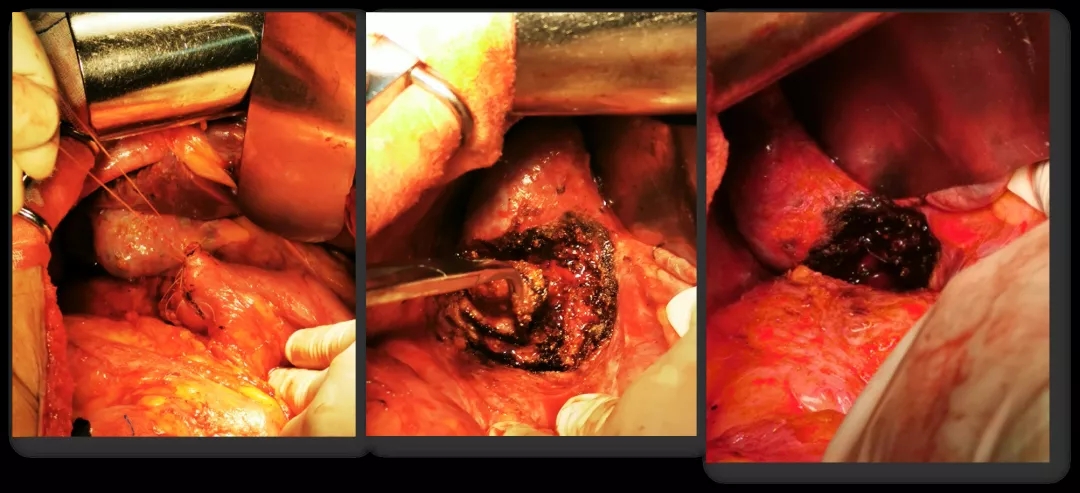

2016.10.26行三次减瘤术(乙状结肠部分切除侧侧吻合+腹盆腔减瘤+腹膜后淋巴结切除),术后无肉眼残留。

术中所见

再次减瘤术